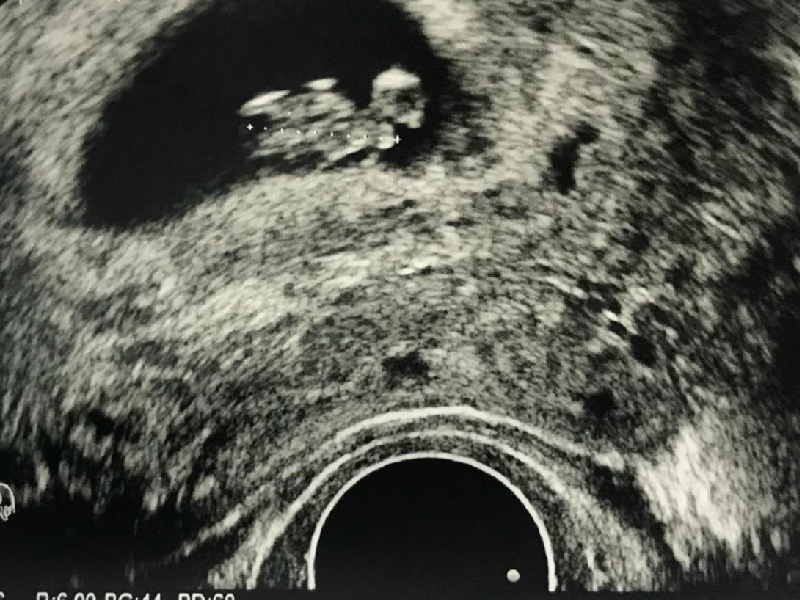

已婚男子在醫院做身體檢查,沒想到當一週後拿到結果,報告中竟然寫有子宮,讓這名人夫當場傻眼! 這起發生在湖南永州的事件,42 歲的唐姓男子爆料稱,他在某醫院健檢後報告單查出子宮,這名人夫當時嚇到一整天沒有心情吃飯。 ![]() 從網傳健檢報告顯示,人員性別一欄為男,而在下方的檢查結果中卻顯示該男子查出了子宮,並有子宮呈前位、形態規則、壁薄內清等報告結果。 ![]() 男子以為自己得了怪病,事後回到醫院,沒想到工作人員解釋,是數據搞錯了,是前面一名檢測者的數據沒有刪除,直接黏到唐男的報告上,醫院事後除了道歉還表示男子可以再來醫院做一遍健檢。不過唐男表示,他會換一家醫院做健檢。 |